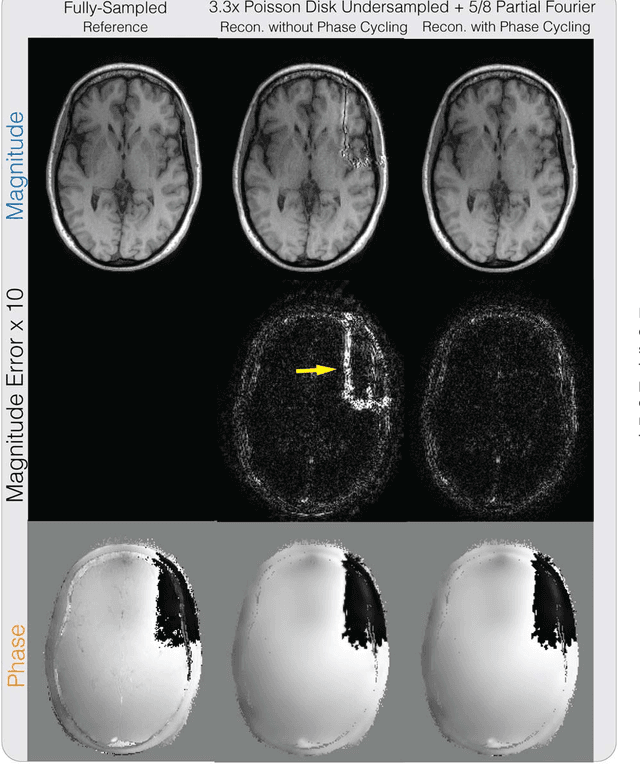

Purpose: To develop a general phase regularized image reconstruction method, with applications to partial Fourier imaging, water-fat imaging and flow imaging. Theory and Methods: The problem of enforcing phase constraints in reconstruction was studied under a regularized inverse problem framework. A general phase regularized reconstruction algorithm was proposed to enable various joint reconstruction of partial Fourier imaging, water-fat imaging and flow imaging, along with parallel imaging (PI) and compressed sensing (CS). Since phase regularized reconstruction is inherently non-convex and sensitive to phase wraps in the initial solution, a reconstruction technique, named phase cycling, was proposed to render the overall algorithm invariant to phase wraps. The proposed method was applied to retrospectively under-sampled in vivo datasets and compared with state of the art reconstruction methods. Results: Phase cycling reconstructions showed reduction of artifacts compared to reconstructions with- out phase cycling and achieved similar performances as state of the art results in partial Fourier, water-fat and divergence-free regularized flow reconstruction. Joint reconstruction of partial Fourier + water-fat imaging + PI + CS, and partial Fourier + divergence-free regularized flow imaging + PI + CS were demonstrated. Conclusion: The proposed phase cycling reconstruction provides an alternative way to perform phase regularized reconstruction, without the need to perform phase unwrapping. It is robust to the choice of initial solutions and encourages the joint reconstruction of phase imaging applications.